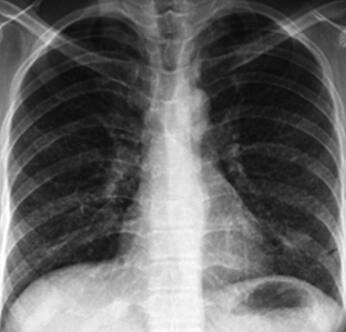

9.头CT:未见异常;胸部X线检查:双肺纹理粗乱(图1)。

图1

检查结果示胸部X线发现双肺纹理粗乱,考虑为感染性发热可能性大,可以给予抗感染治疗,覆盖前期治疗未覆盖的非典型致病菌,如支原体及衣原体,完善胸部CT。颈强直为脑膜刺激征,引起脑膜刺激征的原因较多。此处,我们需要分析感染性脑膜炎: